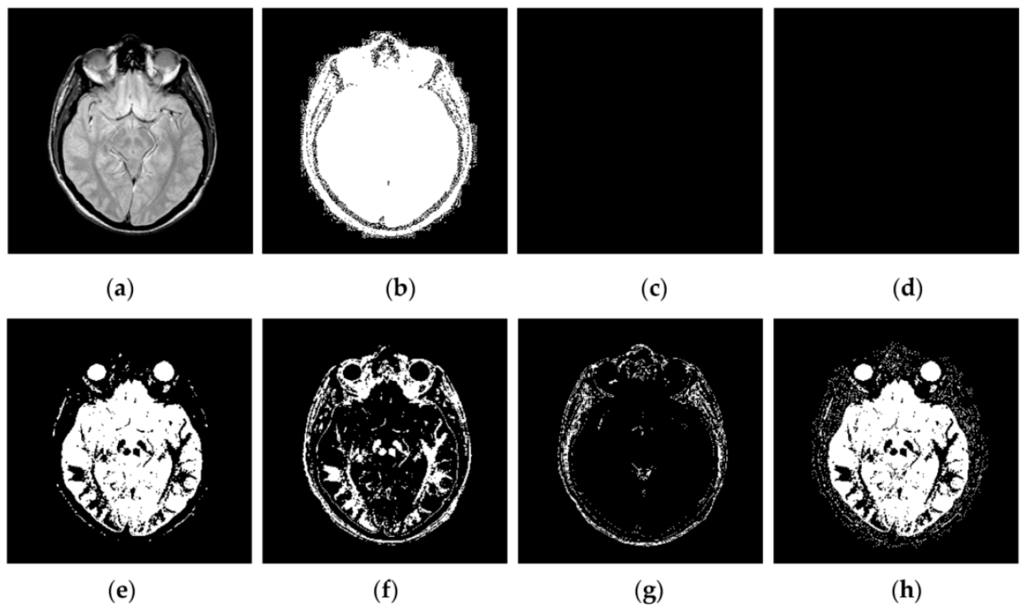

4.2. Visual Comparisons of Fused Results